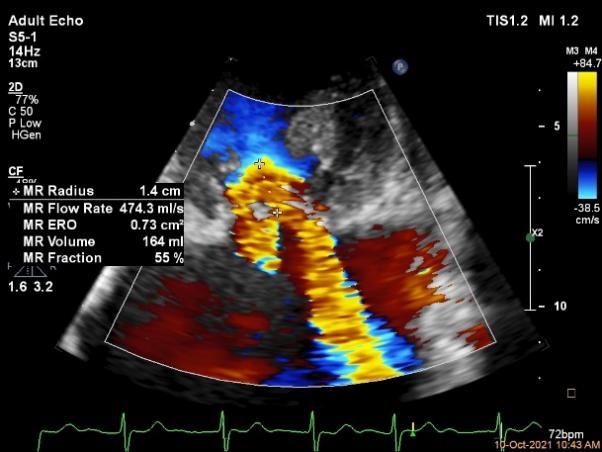

术前超声评估结果

术前超声诊断

3D-color MV view:极大量返流,1、2区均有受累

Qlab软件勾画估测瓣口面积约:6.23cm²